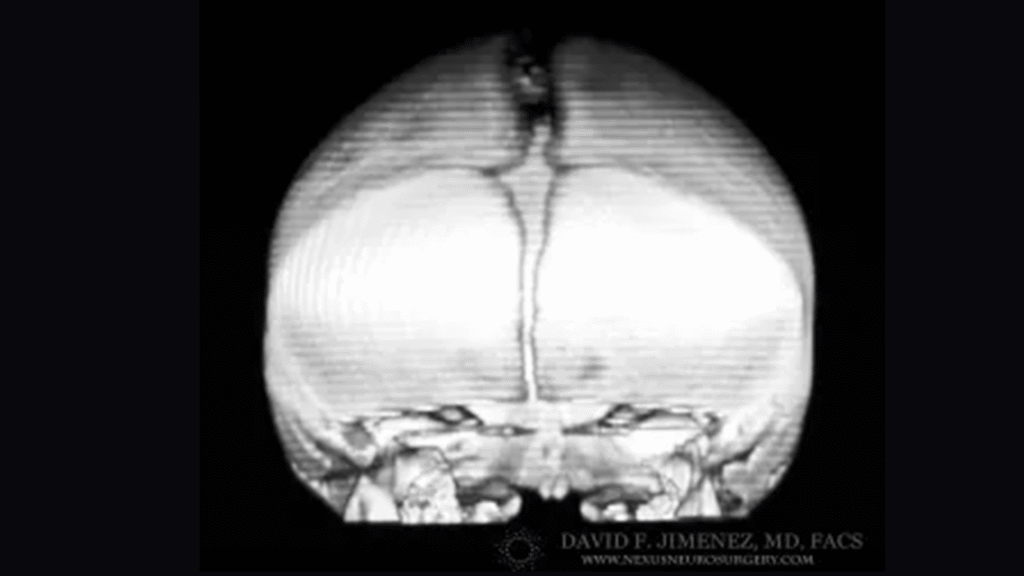

At El Paso Craniofacial Team, the primary treatment for craniosynostosis is surgery. First performed in the late 1800s, surgical approaches have continued to evolve and improve. The two main approaches are Calvarial Vault Remodel (CVR) and endoscopic-assisted surgery, with each tailored to the child’s age, the affected suture, and the severity of the condition.